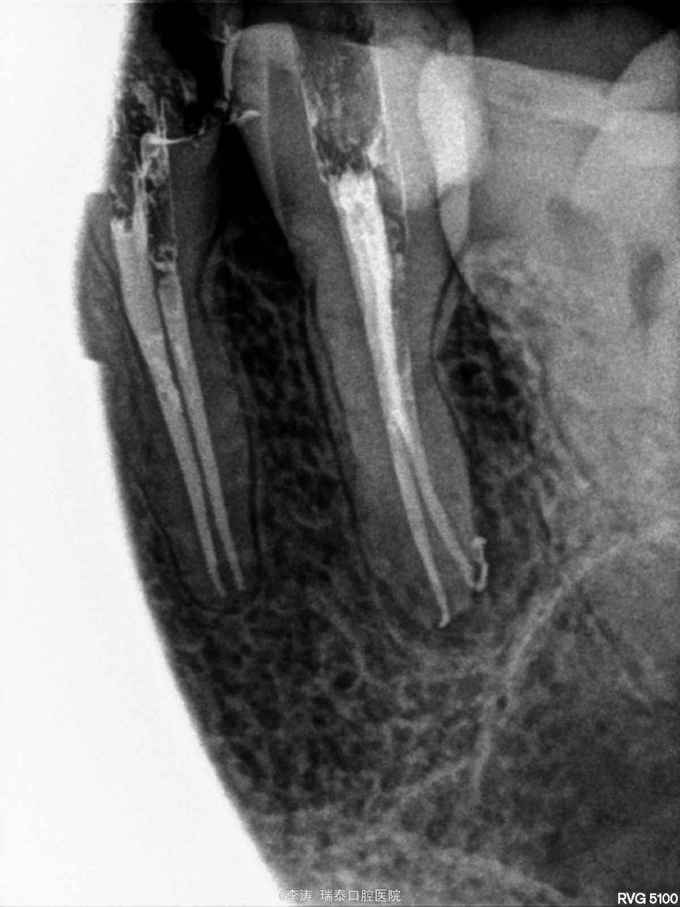

局麻下14,15开髓拔髓,封药一周,复诊行根管预备,TF均预备至2506,但放示踪尖时15牙2506的牙胶能顺利到达工作长度,14牙却无法到位,再次疏通预备冲洗后也无济于事,无奈只能用2504牙胶示踪充填。